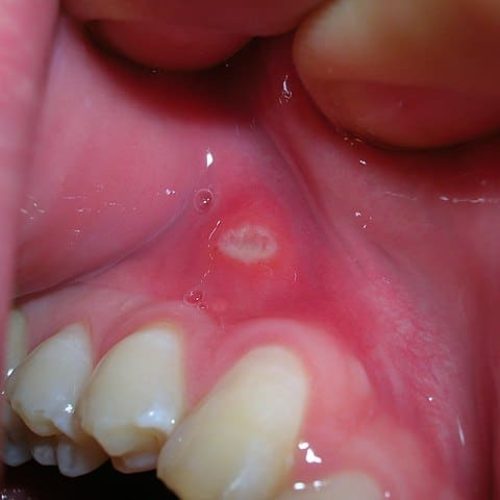

Aphthen - Behandlung und Diagnose vom Online-Hautarzt erhalten